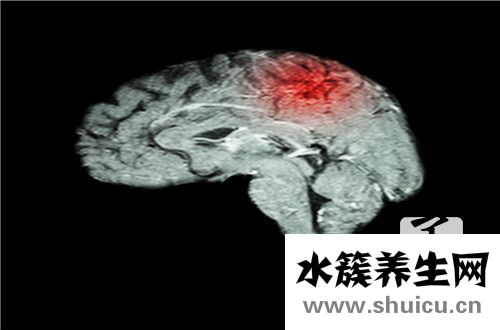

膜蛋白腦病可能是許多人不知道它是什么的病,許多人也不知道它的病因。 因此,每個人都必須先了解其原因和癥狀,然后才能理解。 它是不治之癥嗎? 實際上隨著醫療技術的發展,許多疾病可以治愈。 膜蛋白...

頭部有問題的人通常需要手術治療。 盡管進行手術治療的風險因素很高,但是如果您沒有進行手術,則可能會更快地失去生命。 腦膿腫是一種惡性疾病,因此在腦膿腫手術后,有人可以活多久? 該問題取決于手術...